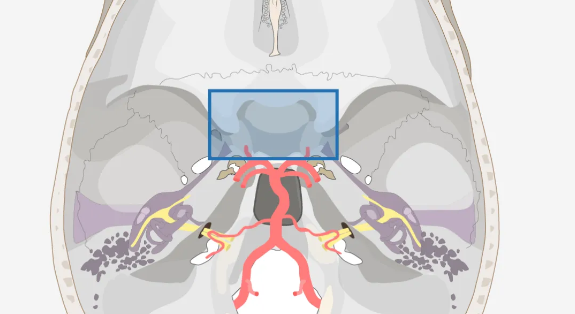

鞍区在哪里?

我们可以想象一下:从眉心再往里大概四五厘米的位置,这是颅中窝中央部的蝶鞍及其周围区域。因为形似马鞍,因此被称为鞍区。

地方虽然不大,只有大约5.5平方厘米,却是众多关乎生命结构的汇集地——如颈动脉、基底动脉、海绵窦、垂体、下丘脑、视神经等多组颅神经等......

视神经与视力息息相关,垂体柄则影响着内分泌功能,下丘脑则决定着患者的认知能力和术后的内分泌状态。

这个手术区域非常精细,一旦出现误差,就可能导致不可逆的神经损伤,这就要求医生在切除肿瘤的过程中,要再三权衡风险,及时做出取舍。